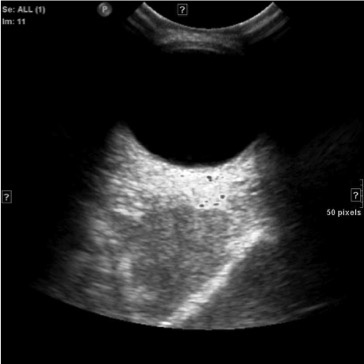

When treating small LM cysts, US guided injection can be performed slowly and in a controlled way watching the agent in real time spread through a geographic area of the lesion. Often multiple needle punctures will be needed to fill a lesion. We use this technique for injection of Doxy and Bleo foams.

MRI of small LM cysts (top), US of needle injecting individual cysts (left), photo of US guided technique for small cyst puncture (right).